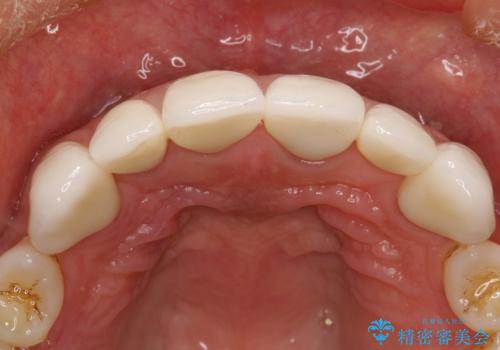

前歯のかぶせ物をオールセラミックへ 形を含めて理想の前歯へ

前歯の合計6本をオールセラミッククラウンにする計画としました。

以前に装着されていたものは全て連結されており、清掃性があまり良くありませんでした。

一つ一つを独立したかぶせ物を装着することで、フロスも可能になり、清掃性が向上しました。